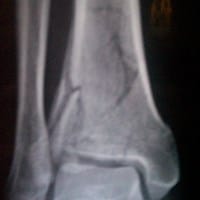

Su opinión fractura

respondió: Bien. ¿En dónde vive usted? ¿A qué se dedica? Definitivamente es una fractura difícil, no puedo ver bien en las imágenes que son muy pequeñas, pero parece verse un trazo articular. ¿O hay varios? ¿Lo operaron o solo yeso? ¿Qué otros tratamientos le...